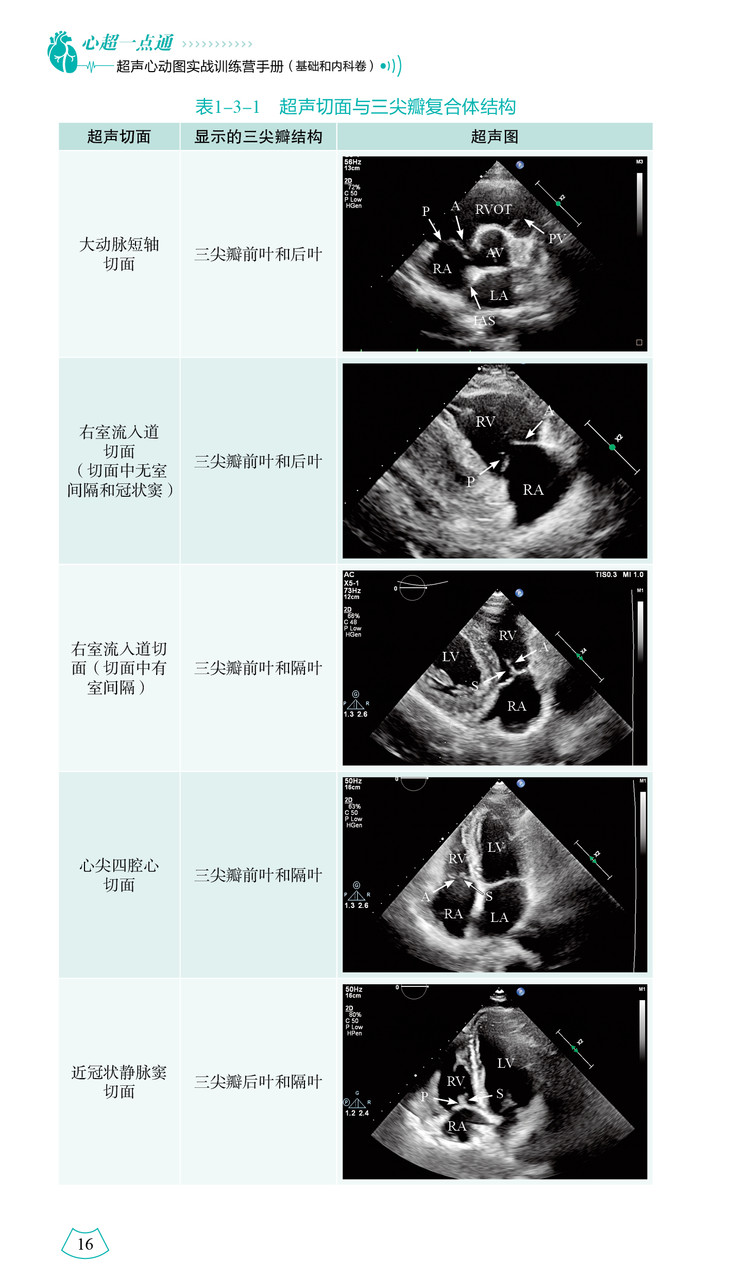

本书详尽阐述了心脏的解剖结构并配以对应的超声图像,从疾病的病理生理出发,分析心脏的结构和功能改变,将解剖结构、血流动力学变化与临床和超声表现融为一体,以示意图、表格的形式进行总结和升华,方便读者进一步理解、掌握各类心血管疾病的诊断及鉴别诊断。基于超声医师兼顾临床及科研工作的情况,本书采用 “训练营”的形式,通过教学视频、超声人体模型及超声演示等对心血管的解剖结构和各种超声技术进行介绍,并设定具体的临床背景进行实战演练,以通俗形象的语言讲解心脏疾病的超声诊断思路。

本书参考超声心动图最新指南和共识,涵盖正常心脏的超声解剖、超声心动图常用技术及超声心动图从常见病到罕见病的诊断方法三大部分。